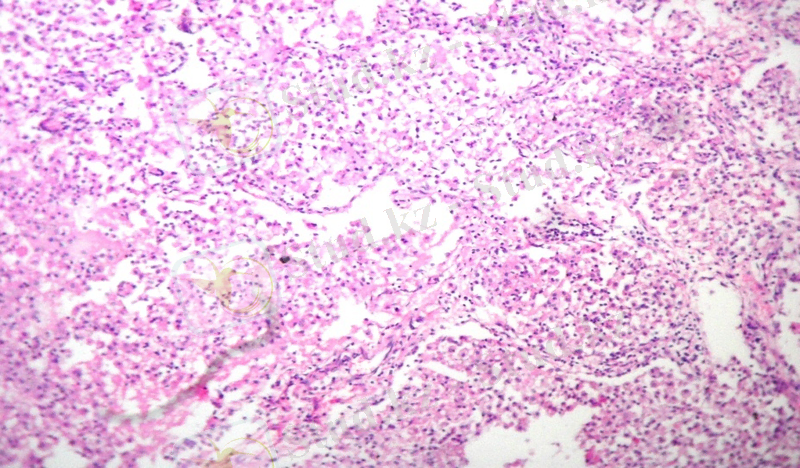

Микроскопиялық зерттеулерде каверналар әдеттегідей үш қабаттан тұрды. Фиброзды қабат жіңішке болды, грануляциялық қабаты нашар жетілген, аз мөлшерде лимфоидты элементтерден, нейтрофильдерден, макрофагтардан тұрады, бірлі-жарым эпителиоидты және Пирогов-Лангханс жасушалары кездесті. Казеозды некроз қабаты өте көлемді болды. Кавернаның айналасындағы өкпе паренхимасында көптеген себінді ошақтар анықталды, олардың ортаңғы бөліктерінде казеозды некроз, айналасында сирек орналасқан эпителиоидты және Пирогов-Лангханс типті көп ядролы алып жасушалар анықталады. Перикавитарлы аймақтарда сегментарлы және полисегментарлы серозды пневмония ошақтары анықталып, серозды экссудаттың казеозды некрозға ұшырауы нәтижесінде сегментарлы казеозды пневмония дамыған (1 сурет) . Казеозды ошақтардың ортаңғы бөлімдерінде ыдырау үрдістері дамып, жаңадан пневмониогенді қуыстар пайда болды. Казеозды массаларда көп мөлшерде ТМ анықталды (2 сурет) . Үлкен бронхтарда гранулематозды мезобронхиттер дамыды, ал субсегментарлы және кіші бронхтарда казеозды бронхиттер анықталды, олардың қабырғаларының сегментарлы және тоталды еруі байқалды (3 сурет) .

1-ші сурет. Казеозды пневмония ошағы. 2-ші сурет. Өкпе тінідегі ТМ жинақталуы

Гематоксилин және эозин бояуы. Ziehl-Neelsen бояуы.

Үлкейту х 200. Үлкейту х 400.